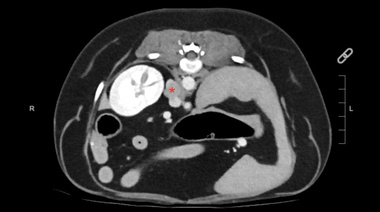

Cardiología veterinaria

RVC: Nueva técnica para el tratamiento de la enfermedad degenerativa de la válvula mitral en perros

01/12 | El Royal Veterinary College, referente global en medicina veterinaria, incorporó una nueva alternativa para el tratamiento de la enfermedad degenerativa de la válvula mitral en perros: la reparación transcatéter de borde a borde, una técnica mínimamente invasiva que ofrece mejores resultados clínicos y una recuperación significativamente más rápida para los pacientes caninos.